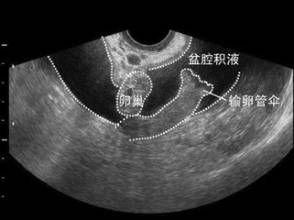

並發盆腔瘀血患者,可有月經增多;卵巢功能損害時,可有月經失調;輸卵管粘連阻塞時,可致女性不孕。

4.不孕

不孕是盆腔積液最常見的症狀,如果患有盆腔炎導致輸卵管堵塞,就會出現不孕,臨床檢查時發現,患者的子宮位置後傾,子宮活動受到限制,或者是發生了粘連。

檢查

盆腔積水檢查對識別來自輸卵管、卵巢及腸管粘連形成的包塊或膿腫有85%的準確性。一般用來診斷較為嚴重的盆腔炎。

盆腔積水可詳細結合病史、症狀以及體症等明確是正常積液還是異常積液。如確診為異常積液則要明確導致積液的原因,病因性診斷是關鍵。

抽取積液是明確診斷的主要手段,適用於有性生活的婦女。